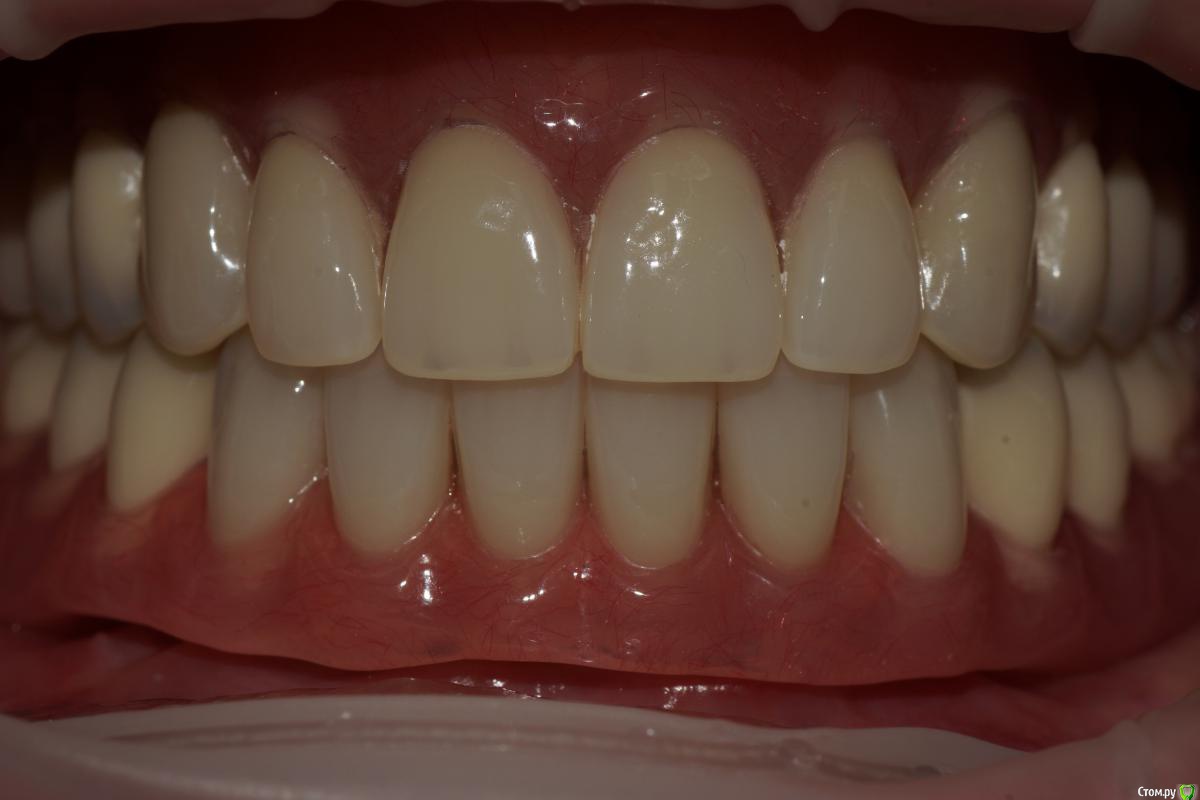

stomalolog Опубликовано 25 ноября, 2016 Поделиться Опубликовано 25 ноября, 2016 Фото улыбки.Красиво, но немного молодые зубы для пациентки? 1 Ссылка на комментарий

togrul Опубликовано 25 ноября, 2016 Автор Поделиться Опубликовано 25 ноября, 2016 Красиво, но немного молодые зубы для пациентки?Спасибо. пациентка сама захотела форму и цвет) Ссылка на комментарий